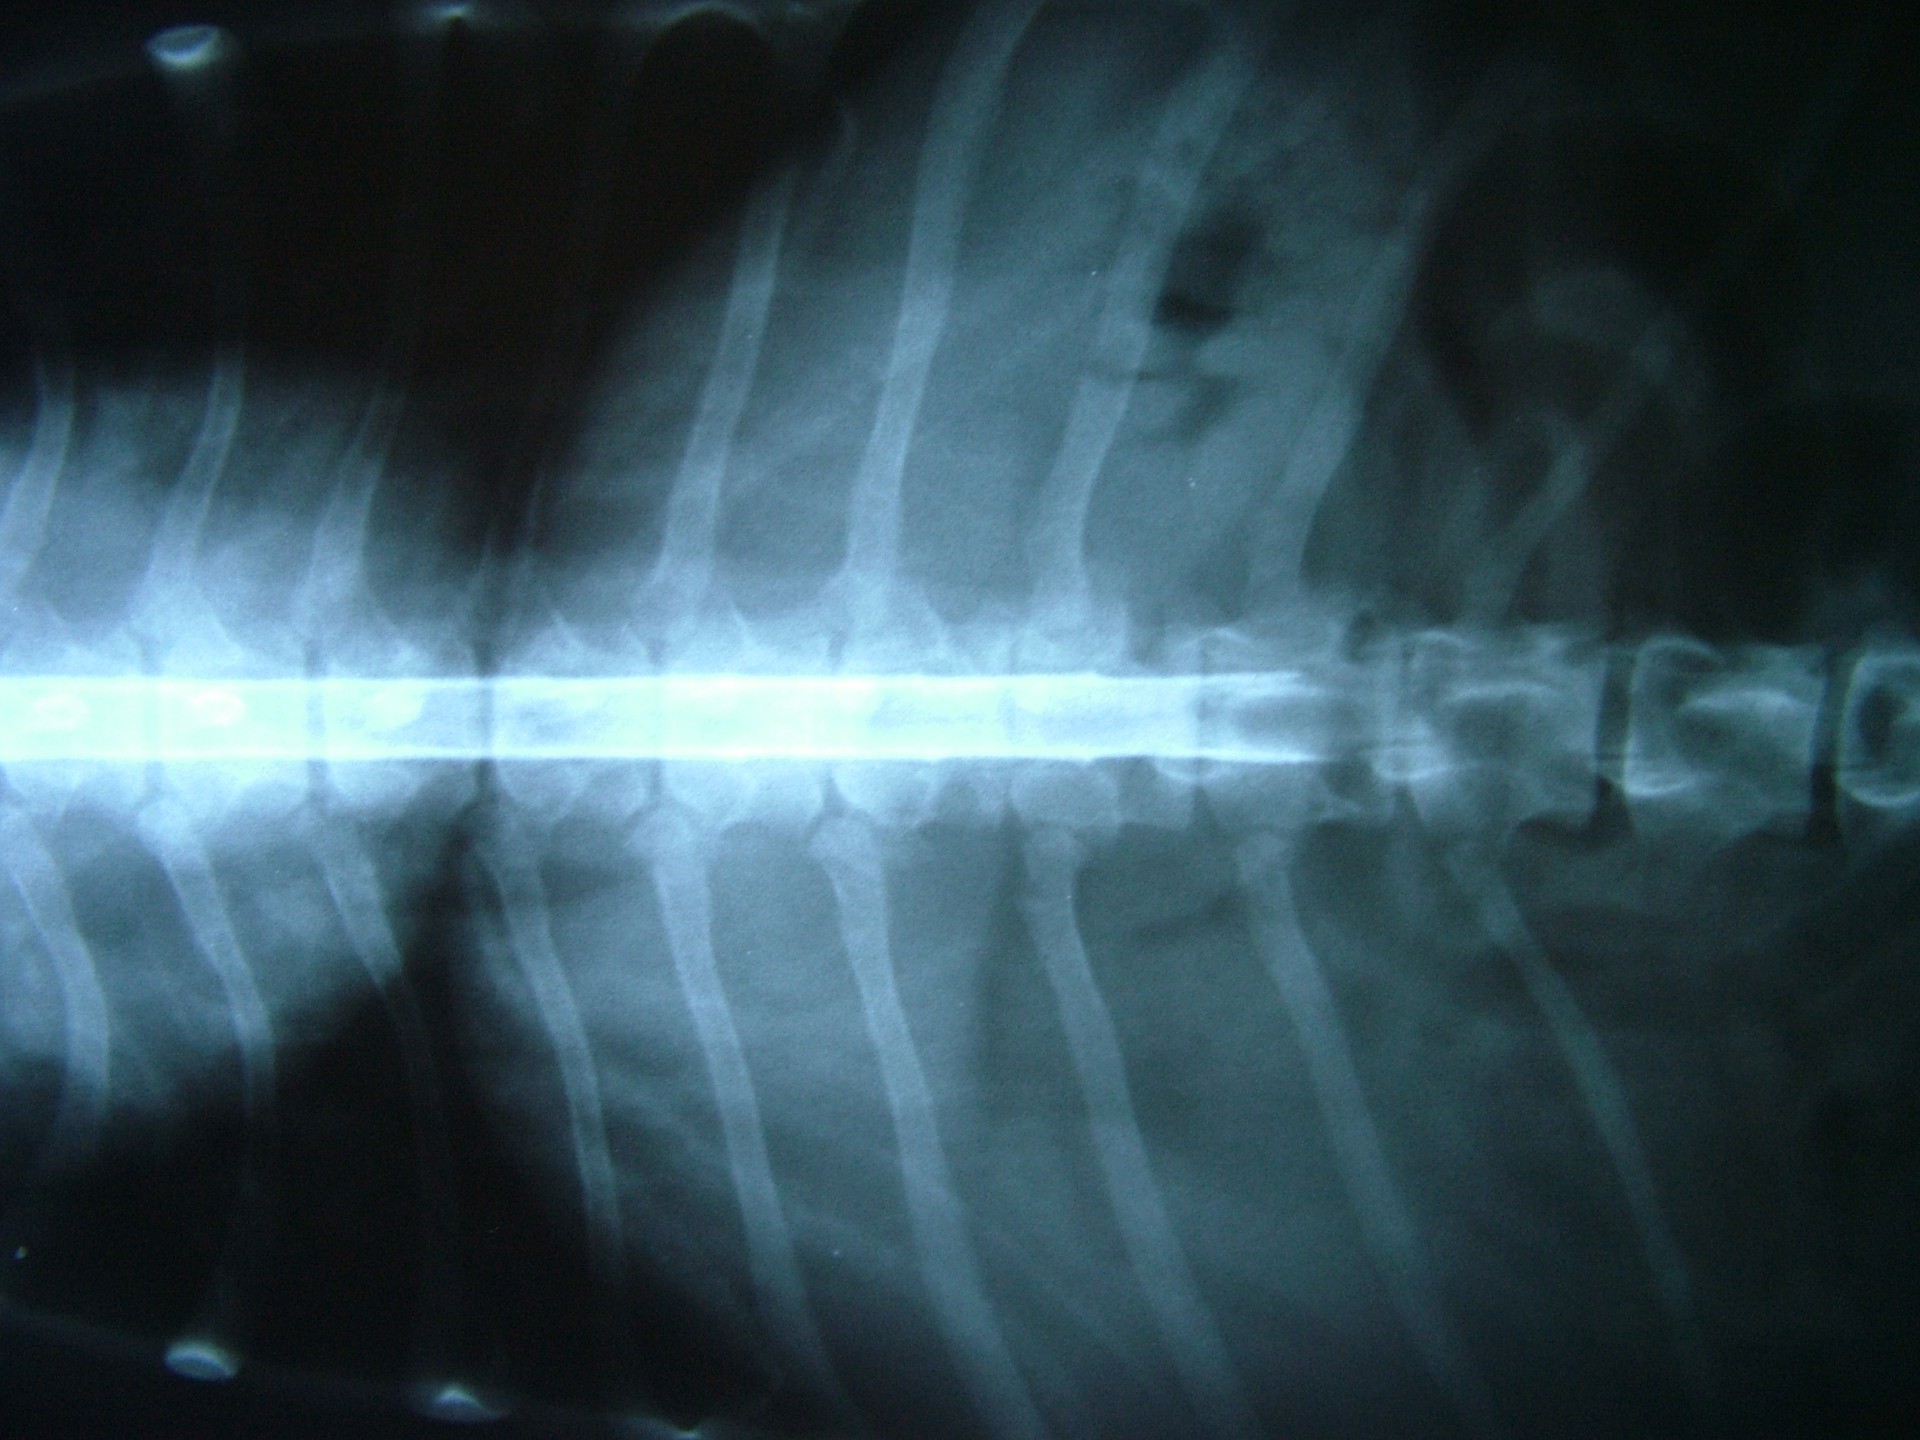

Az alapos neurológiai vizsgálattal és natív röntgen felvétel készítésével ugyan a gerincvelő sérülésének helye megjósolható, a porckorongsérv pontos lokalizációjának meghatározásához kiegészítő vizsgálatra, a gerinccsatorna megfestésére (myelographia) vagy egyéb képalkotó vizsgálatra (CT, MRI) van szükség.

A myelographia során egy, a röntgen felvételen látható kontrasztanyagot juttatunk a gerinccsatornába, pontosan a gerincvelő és az azt körülvevő un.: kemény gerincburok (dura mater) közé. Ezt követően az állatot kb.: 45°-os szögben egy erre alkalmas asztalon lógatjuk, így a kontrasztanyag addig folyik a gerinccsatornában, amíg a gerincvelőt összenyomó porckoronghoz ér. Az így készített RTG felvételen az összenyomatást okozó előesett porckorong helye egyértelműen, az oldaldetermináció pedig általában meghatározható.A myelographia nagy előnye, hogy a betegvizsgálat helyén, azonnal elvégezhető, hátránya, hogy az altatásban történő vizsgálat invazív beavatkozás, mely után különféle szövődmények alakulhatnak ki.